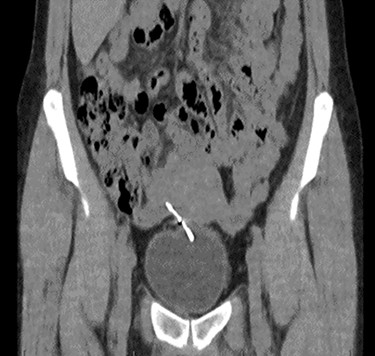

Computed tomography (CT) scan including a urographic phase revealed an IUCD in the vesico-uterine space, with one horn embedded into the bladder (Figs 2–4).

Axial CT urinary tract image demonstrating the device lying between uterus and bladder.